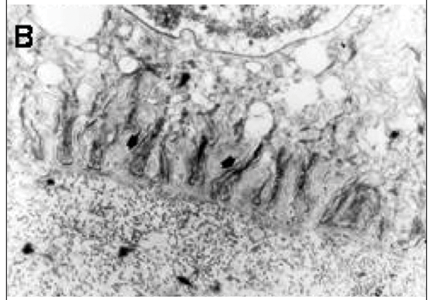

Cortes transversais das membranas controles mostraram células epiteliais interconectadas através de complexos juncionais, com vacúolos intracelulares e microvilos na superfície apical. Na porção basal das células epiteliais, interdigitações foram observadas com a porção anterior da membrana basal, que dividia o epitélio do estroma colagenoso subjacente (Figuras 1A e 1B).

Em amostras de membrana amniótica preservada em meio glicerol/MEM, foi observado aumento da altura do epitélio e da espessura da membrana basal, com boa preservação das junções intercelulares e das interdigitações entre a face basal do epitélio e a membrana basal (Figuras 2A e 2B). Nas membranas preservadas com DMSO, foi evidenciada perda da integridade tecidual, com aumento da vacuolização das células epiteliais, diminuição das junções intercelulares, perda das interdigitações entre a face basal do epitélio e membrana basal e destacamento do epitélio da membrana basal (Figuras 3A e 3B).